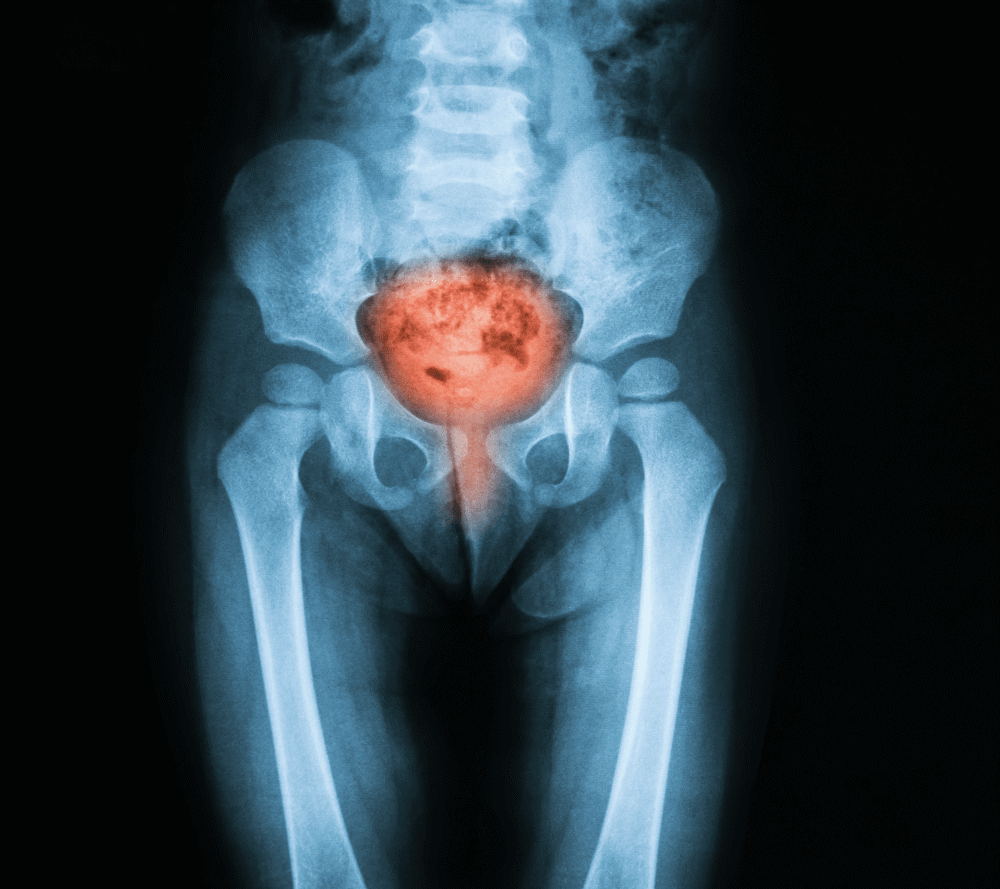

Cystitis refers to bacterial infection of the bladder, which causes it to become inflamed. It is a common type of lower urinary tract infection (UTI) that occurs when bacteria enter the bladder via the urethra.

Image Credit: Suttha Burawonk / Shutterstock.com